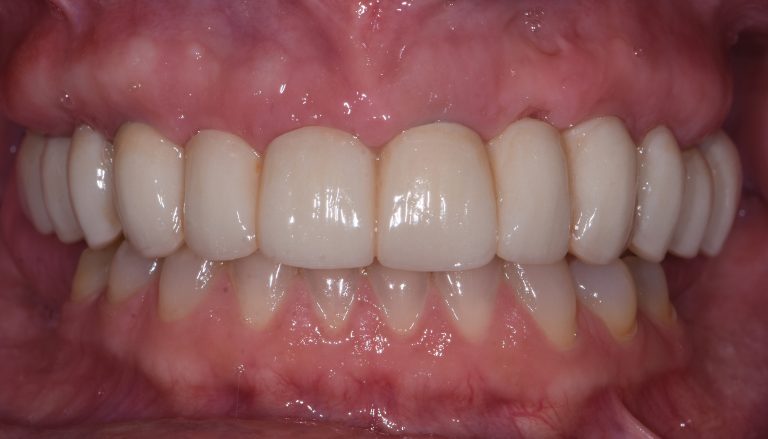

Once the implant has been fully integrated with the bone, the next phase begins: the fabrication and placement of your permanent artificial tooth or teeth. This typically requires two to four appointments and combines the technical and artistic aspects of prosthodontics. Dr. Leong uses advanced technology and his expertise in dental aesthetics to create lifelike, durable restorations that blend seamlessly with your natural smile.

Once your final dental prosthetics are attached, you’ll be able to eat, speak, and smile confidently, just like you did with your original teeth.